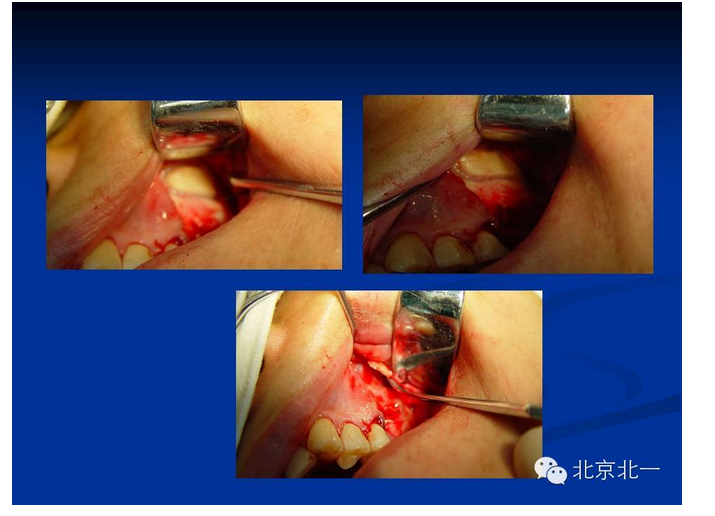

擅長:種植外科,尤其專長復(fù)雜牙種植,自體骨移植同期種植,上頜竇底內(nèi)外提升同期種植技術(shù),美學(xué)區(qū)種植技術(shù),即刻種植外科與即刻負(fù)重技術(shù),軟組織成形外科種植技術(shù)及全口無牙頜ALL-ON-FOUR技術(shù),種植并發(fā)癥和種植急癥處置等手術(shù)治療,從事口腔頜面外科,正頜外科、頜面部整形、微創(chuàng)拔牙,笑氣無痛舒適種植十余年。